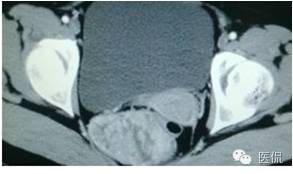

女,37岁,体检超声发现盆腔包块一周。无其他异常。

CT平扫(CT值23HU)